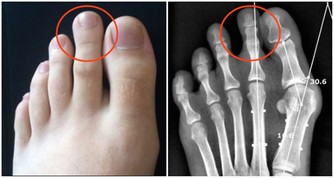

9. 請大家記住一個原則,吃植物性的東西,一定要佔80%

動物性的東西只能佔20%。

我們現在相反了,所以很多病都來了,肥胖也來了,糖尿病也來了,痛風也來了。